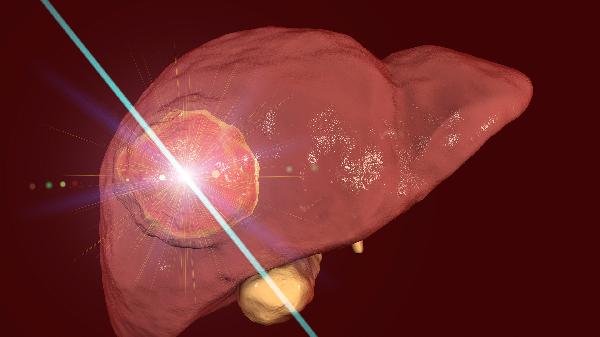

5、肝臟體積縮小:

影像學(xué)檢查顯示肝臟進(jìn)行性萎縮,肝濁音界縮小。超聲可見(jiàn)肝實(shí)質(zhì)回聲不均,門靜脈血流減少。肝臟活檢可見(jiàn)大塊或亞大塊壞死,但臨床通常避免有創(chuàng)檢查。